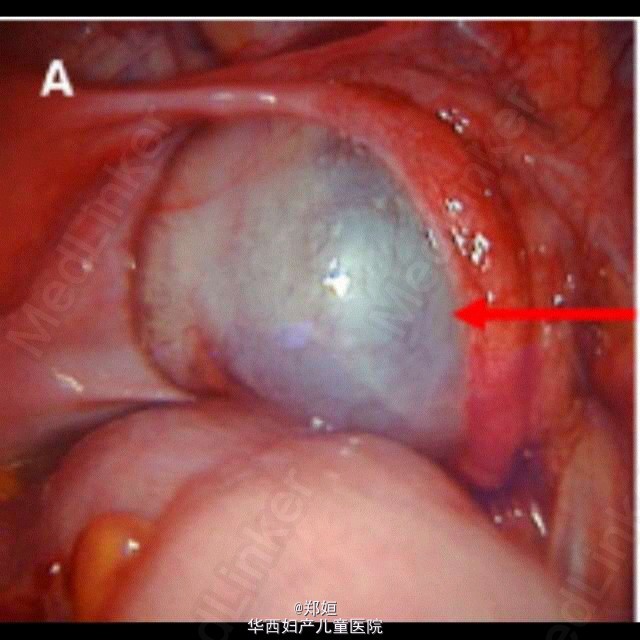

最近看的一个病例,给大家分享。 27岁女性,因出现幻觉入院。 既往:10天前出现流感样病症。 神经科检查示患者有顺行性遗忘症状和行动障碍,格拉斯哥昏迷评分从10分降到6分,全身CT检查示右侧卵巢有直径4cm的囊性包块。